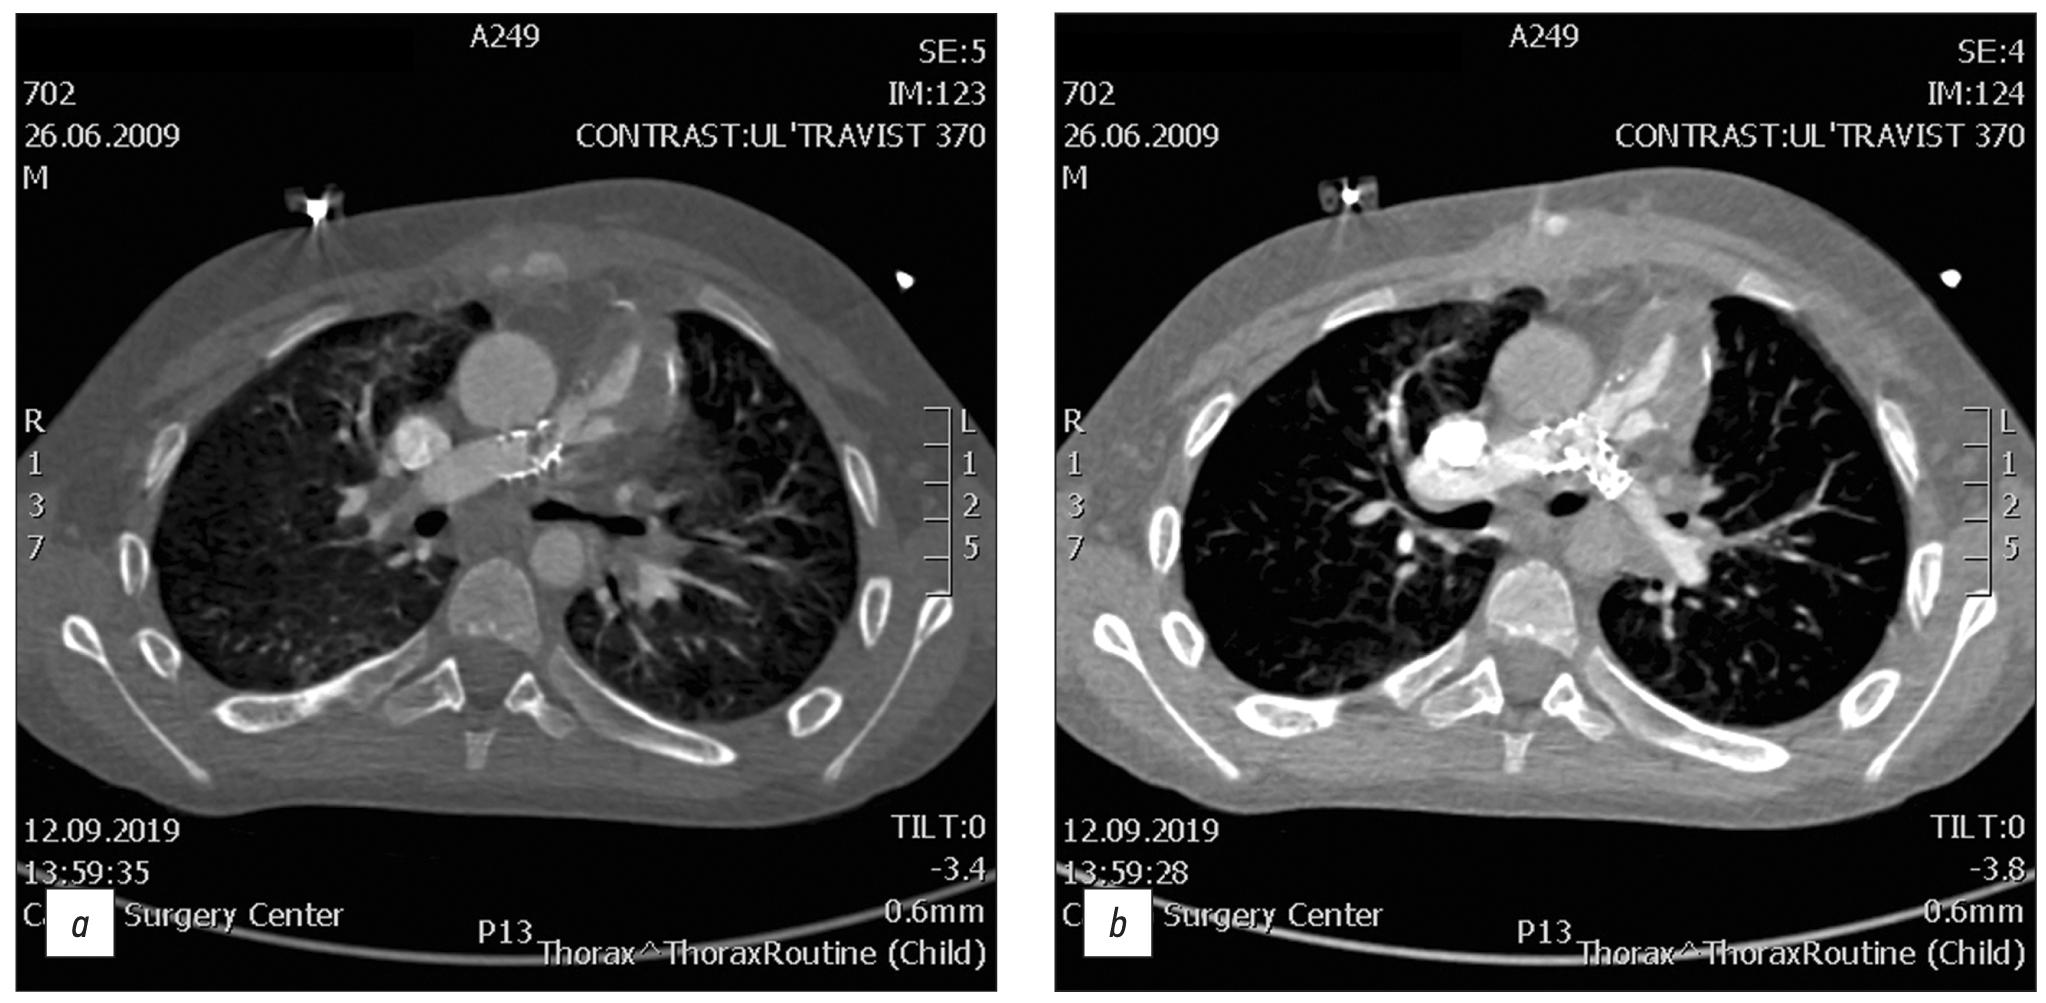

BACKGROUND: Tetralogy of Fallot represents 7–10% of all cases of congenital heart disease, as it occurs in approximately 0.5 per 1,000 live births and is the second most common form of complex congenital heart disease. Advances in diagnosis, surgical techniques, and postoperative treatment have led to an increasing number of patients reaching adulthood, with a dramatic increase in the survival rate to almost 90% at 30 years, thereby creating a need for long-term monitoring of certain anatomic parameters to identify complications in a timely manner. This study aimed to investigate the frequency of computed tomography detected complications after radical correction of Tetralogy of Fallot in pediatric patients.

MATERIALS AND METHODS: A retrospective analysis was conducted on 613 patients with Tetralogy of Fallot from October 2011 to June 2020. The study included a total of 116 patients (69 men and 47 women) who experienced complications after a repair of Tetralogy of Fallot, as identified by computed tomography. At the time of repair of Tetralogy of Fallot, the patient’s average age ranged from 10 to 36 months (mean: 12 months), average body weight was 21 kg, average height was 105.4 cm, and average body surface area was 0.74 m2. The patients’ median age at the time of the computed tomography examination was 17.5 years (age range: 7–36 years).

RESULTS: Among the 116 patients who exhibited complications after an repair of Tetralogy of Fallot, 49 had a pulmonary artery stenosis, 92 had a pulmonary artery branch stenosis (56 of them of the left main pulmonary artery branch, and 36 of them of the right main pulmonary artery branch), 8 had a right ventricular outflow tract stenosis, 32 had a ventricular septal defect, 1 had a shunt thrombosis, 12 had a postoperative deformation of the pulmonary artery, 10 exhibited a marked right ventricular dilatation, 2 had an right ventricular outflow tract aneurysm, and 6 suffered from conduit calcification and stenosis. Moreover, patients with left main pulmonary artery branch stenosis had a 6.5 times greater chance of developing an right main pulmonary artery branch stenosis in (p <0.001).

CONCLUSION: The most frequently computed tomography detected complications after a repair of Tetralogy of Fallot were pulmonary artery stenosis and pulmonary artery branch stenosis. Patients with pulmonary artery stenosis and pulmonary artery branch stenosis exhibit no significant differences in terms of age, anthropometric parameters (height, weight, and body surface area), and gender distribution in the presence or absence of different stenosis types (pulmonary artery, right main pulmonary artery branch, or left main pulmonary artery branch). However, an right main pulmonary artery branch stenosis increases the chances of developing an left main pulmonary artery branch stenosis.